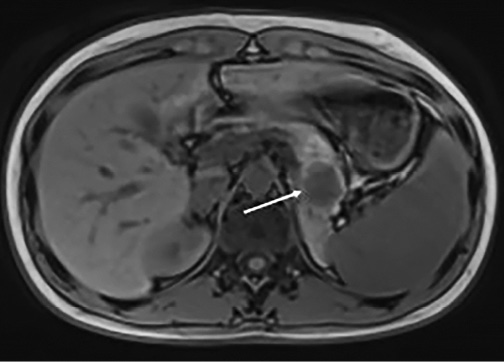

15 m. pacientei, gydytai dėl kaulų tuberkuliozės, planinio ligos stebėjimo metu 2023 m. rugsėjo mėn. atliktas magnetinio rezonanso tyrimas. Papildomai nustatytas 2,5×2,2×2,6 cm cistinis darinys kasos uodegoje, turintis solidinio pseudopapilinio kasos naviko radiologinių požymių. 2024 m. sausio mėn. MRT kontrolės metu diagnozuota, kad cistinis darinys padidėjo iki 2,8 cm (1 pav.), o birželio mėn., atlikus KT tyrimą, nustatyta, kad darinys išaugo iki 3,1 cm. Metastazių ar išplitimo nepastebėta, todėl pacientei, baigus antituberkuliozinį gydymą, nuspręsta atlikti kasos naviko rezekciją. Atsižvelgiant į naviko ypatybes ir jo lokalizaciją kasos uodegoje, prieš operaciją aptarta galimybė kartu pašalinti ir blužnį. Pacientei iš anksto atlikti visi būtinieji priešoperaciniai skiepai.

1 pav. Cistinio kasos darinio MRT vaizdas prieš operaciją